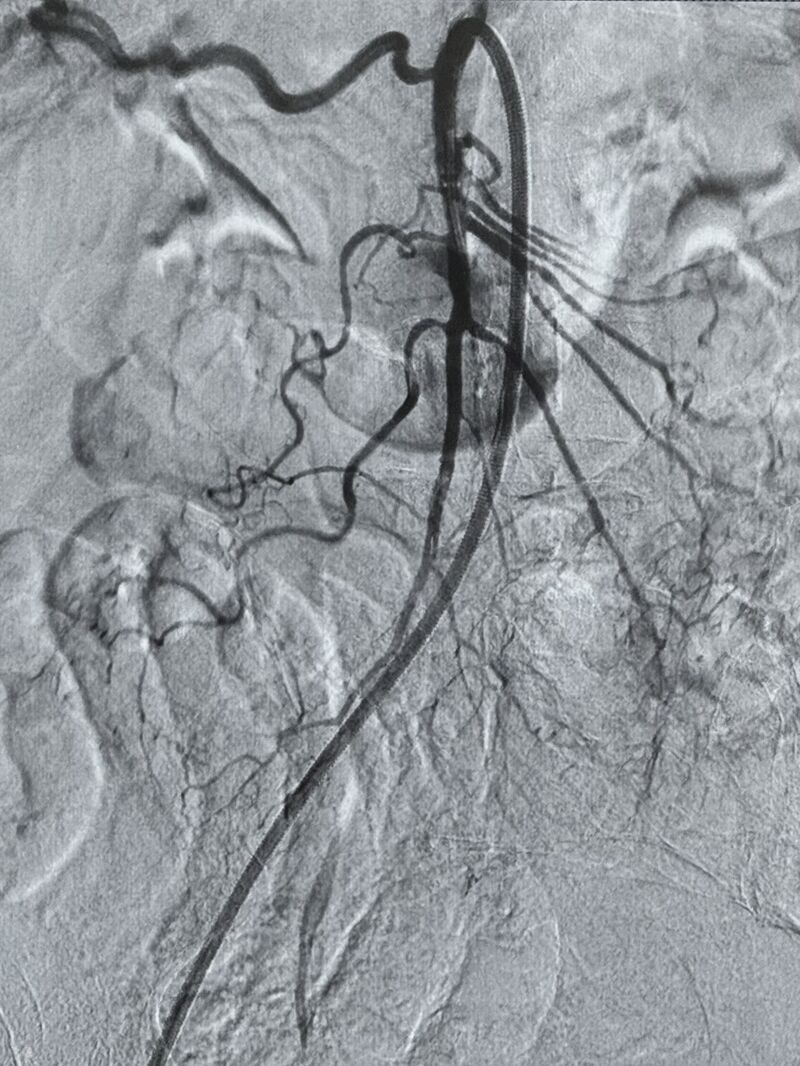

”Revascularization of the superior mesenteric artery (SMA) in a patient with acute mesenteric ischemia.

Selective catheterization of the SMA was performed, and 200.000 Ui bolus of urokinase were infused into the thrombus.

Subsequently, thromboaspiration of the occluded segment was carried out using a CAT-8 catheter (Penumbra).

After achieving recanalization, an additional 200,000 Ui bolus of urokinase was administered.

The final angiographic control demonstrated complete recanalization of the previously occluded artery, with opacification of all colic and jejunal vascular branches.

The patient then continued with an infusion of urokinase at a rate of 120,000 IU per hour.

Pre and post-treatment DSA are shown.